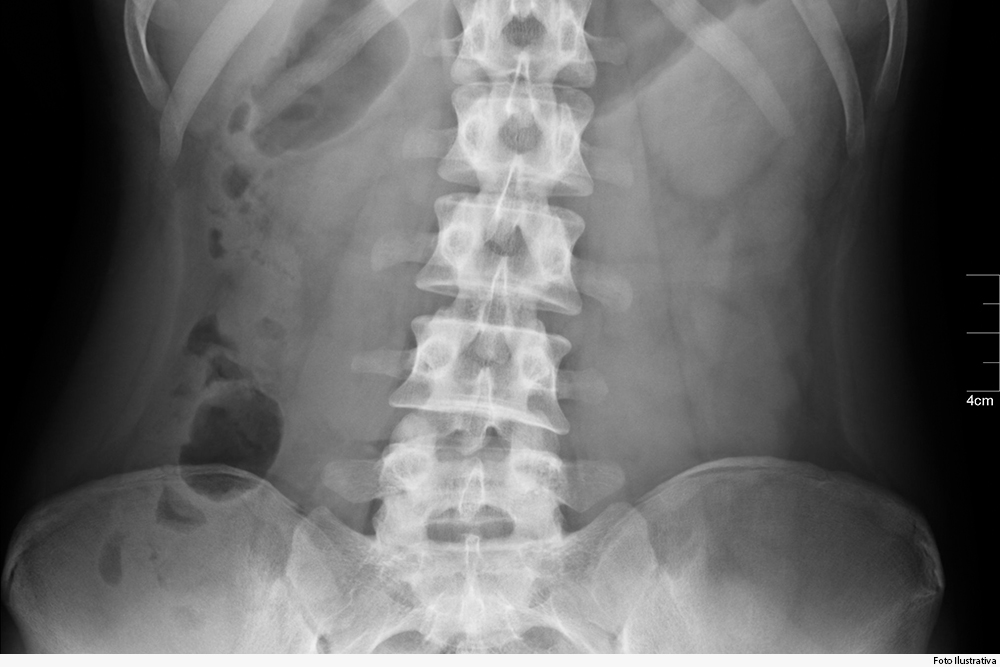

O caso aconteceu em dezembro de 2015, em Contagem. A vítima contou que o ônibus estava em alta velocidade, caiu em um buraco e ela se desequilibrou, caindo sentada no chão do veículo, o que levou a uma fratura numa vértebra da coluna.